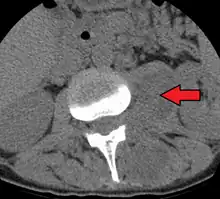

Psoas abscess

Psoas abscess is a collection of pus in the iliopsoas muscle compartment.[1][2] It can be classified into primary psoas abscess (caused by hematogenous or lymphatic spread of a pathogen) and secondary psoas abscess (resulting from contiguous spread from an adjacent infectious focus).[2]

Psoas abscess may be caused by lumbar tuberculosis. Owing to the proximal attachments of the iliopsoas, such an abscess may drain inferiorly into the upper medial thigh and present as a swelling in the region. The sheath of the muscle arises from the lumbar vertebrae and the intervertebral discs between the vertebrae. The disc is more susceptible to infection, from tuberculosis and Salmonella discitis. The infection can spread into the psoas muscle sheath.[3]